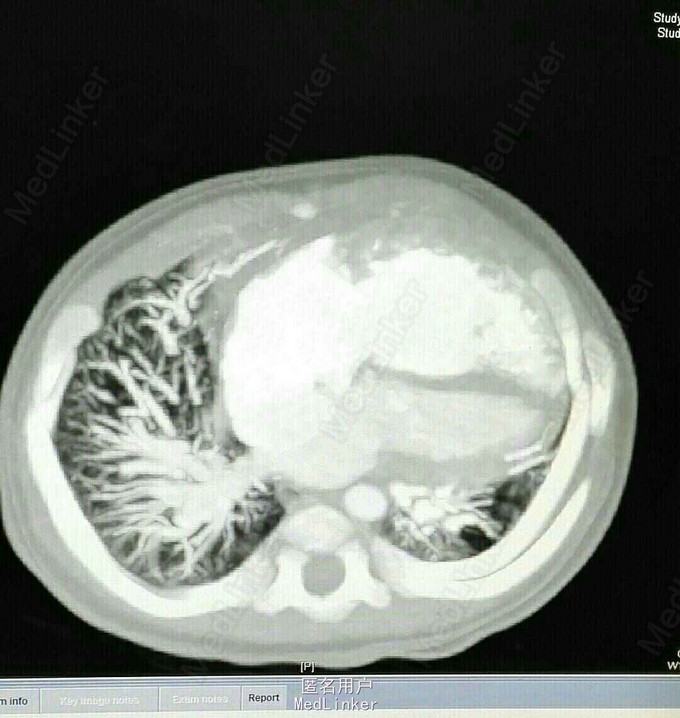

查体 生命体征平稳,双肺呼吸音清,未闻及干湿性罗音,心率规整,于胸骨左缘第二肋间可闻及3/6期收缩期杂音,腹部平软无压痛反跳痛,双下肢无水肿。 辅助检查 心脏彩超示 先天性心脏病 右肺动脉起源于主动脉 动脉导管未闭 三尖瓣反流 肺动脉高压。 心脏CT 先天性心脏病 右肺动脉起源于主动脉 动脉导管未闭 肺动脉高压

诊断 先天性心脏病 右肺动脉起源于主动脉 动脉导管未闭 肺动脉高压 三尖瓣反流 治疗 患者入院后完善各项术前检查及准备在全麻体外循环下行手术治疗 手术过程 仰卧位胸骨正中切口,常规建立体外循环,并体循环下分离并切断缝合动脉导管,充分游离右肺动脉,并将右肺动脉自主动脉离断,6/0丙烯线连续缝合主动脉侧断端。右肺动脉经主动脉下方吻合至主肺动脉侧动脉导管开口。切开右心房,并行下缝合卵圆孔未闭。三尖瓣成型,试水关闭良好,缝合右心房,停机关胸。患者转让监护室治疗2天后转让普通病房术后恢复良好。